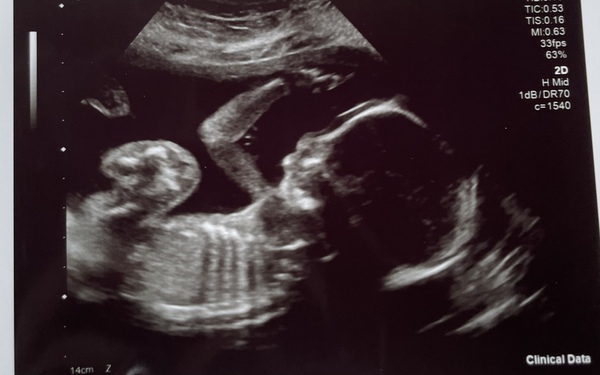

I’m currently 24 weeks pregnant with my second & since getting the results for the combined bloods and screening test at 12 weeks I can’t shake the feeling that there’s something wrong with my baby. My edwards ratio came back as 1:280 with low Papp-a. After the harmony test didn’t work from low fetal DNA I’ve waited until the 20 week scan to see if everything was ok. The scan went ok apart from a slight issue with the heart and have been referred on to a specialist. However to me, my scan picture doesn’t look right. It’s clear, but I can’t see a nasal bone & he looks small and I don’t know. Something just doesn’t look right with it. I’ve inserted a picture of the scan.

Looks fine to my non radiography trained eye. Could you chat over your concerns with your midwife maybe? Scans can often look weird, IMHO.

Remember a scan picture is just one 2d image of a moving 3d baby do depending on the angle things will look weird. The baby's face is likely not in profile so that may be why you can't see the nasal bone.

I agree with others about discussing with your medical team but just to say I agonised over scan pictures with both of my LOs. They turned out to be perfectly healthy but I got so worried that something was wrong and would pick up on the tiniest thing. As PP said, it’s a snap shot of a moving baby and a millimetre of difference in position can create a different image. Anxiety makes your mind run away with you so definitely check in with your midwife and consultants for reassurance.

OP I would say the pic looks great but I can imagine you must be so worried. Can you phone the hospital to ask about it? Maybe the sonographer can have a chat with you. I hope your appointment and further scans come back OK x